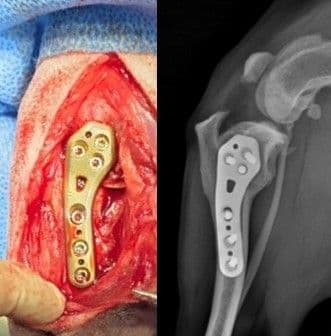

십자인대 수술

TPLO, CBLO, CTWO, 낭외고정술

슬개골 탈구 교정술

TTT, DFO, PTO